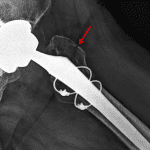

- Left total hip arthroplasty with an acute, minimally displaced periprosthetic fracture of the greater trochanter

- Cortical lucency along the lateral aspect of the upper proximal femoral cerclage wire

- Periprosthetic greater trochanter fracture

Left total hip arthroplasty with an acute, minimally displaced periprosthetic fracture of the greater trochanter.

No joint malalignment.

Cortical lucency along the lateral aspect of the upper proximal femoral cerclage wire concerning for osteolysis.